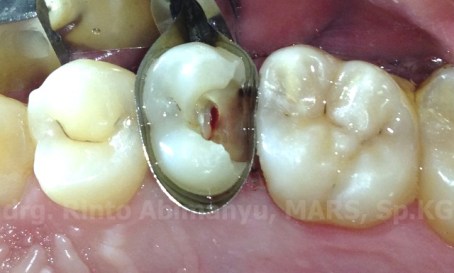

Terlihat karies sudah mengenai pulpa sesuai dengan foto ronsen dan gingiva sebelah distal terlihat sedikit menutupi tepi gigi, maka saya lakukan pemotongan gingiva dengan cauter untuk mempermudah dalam pembuatan dinding distal (artificial wall)

Ini keadaan setelah pemotongan gingiva..